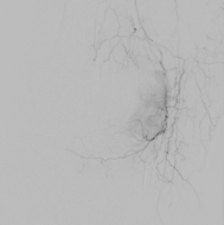

Kniegelenkembolisation

Dabei werden gezielt kleine Blutgefäße, die zur Entzündung und zum Knieschmerz beitragen, durch winzige Partikel verschlossen. Der Eingriff erfolgt schonend über einen kleinen Zugang in der Leiste, meist unter örtlicher Betäubung. Die meisten Patienten spüren bereits kurz nach dem Eingriff eine deutliche Schmerzlinderung und können rasch in ihren Alltag zurückkehren.

Die Kniegelenkembolisation stellt keinen Ersatz für eine Knieprothese dar, sondern dient lediglich der Schmerzbehandlung und kann eine Operation hinauszögern.